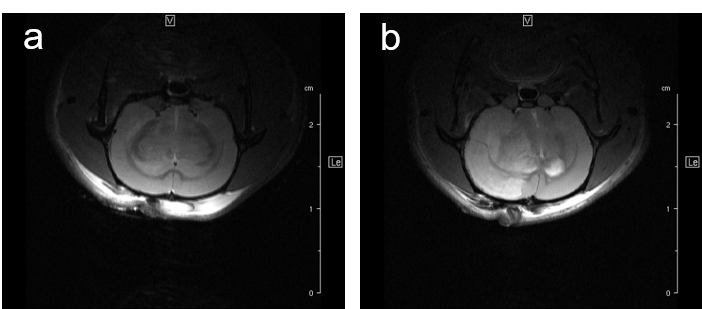

For studying disease pattern of stroke patients, we use a rat animal model with induction of focal cerebral ischemia and follow-up by MRI, Fig.7.

Fig. 7: Infarcted rat brain MRI. For comparison of infarct size of induced infarct right after OP and 24 h later a T2 weighted Spinecho sequence was used: repetition time: 3800 ms, echo time: 18.0 ms, field of view: 35x35 mm2, matrix:512x256 and slice thickness 1.0 mm was used to acquire 12 axial slices.